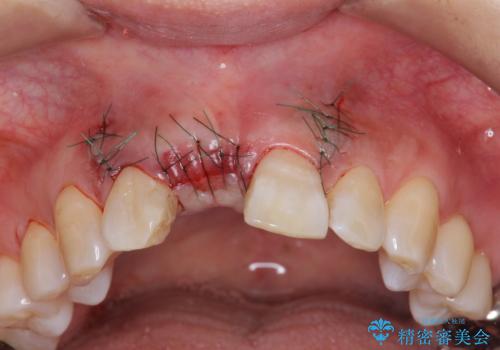

審美的・機能的に良好な位置に埋入するには、骨量が十分ではなかったため骨の造成を併用したインプラント埋入外科手術を行います。

前歯のインプラントを審美的に仕上げるには、インプラント周囲に十分な骨の量と厚みのある歯肉、そして埋入位置の精密な位置付けが重要です。